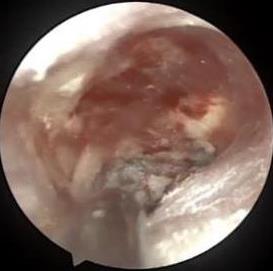

• 耳内镜下耳屏软骨-软骨膜鼓膜修补术后的短期疗效观察

摘要:目的 探讨耳内镜下耳屏软骨-软骨膜鼓膜修补术后的短期疗效。方法 回顾性分析2019年9月-2022年8月该院收治的78例鼓膜穿孔患者的临床资料,患者均采用耳内镜下鼓膜修补术。术后随访3个月,观察鼓膜形态和穿孔愈合情况,记录内镜图像、干耳时间、术前术后听力及耳鸣情况,以及外耳道狭窄等并发症的发生率。结果 术后3个月,鼓膜穿孔愈合率为97.44%(76/78),愈合良好,平均气导听阈较术前明显改善,气骨导间距较术前明显缩小,耳鸣较术前明显改善,差异均有统计学意义(P<0.05)。干耳时间为(4.21±1.12)周。术后出现肉芽5例,再穿孔2例,真菌感染2例,术腔感染、耳屏感染、外耳道狭窄和切口瘢痕各1例,所有患者术后均未发生面神经麻痹和感音神经性聋等严重并发症。结论 耳内镜下耳屏软骨-软骨膜鼓膜修补术是一种安全、有效的手术方法。根据术后愈合规律、内镜下鼓膜和外耳道形态特征,可为鼓膜修补术后正常中耳转归和并发症的诊疗,提供临床参考。